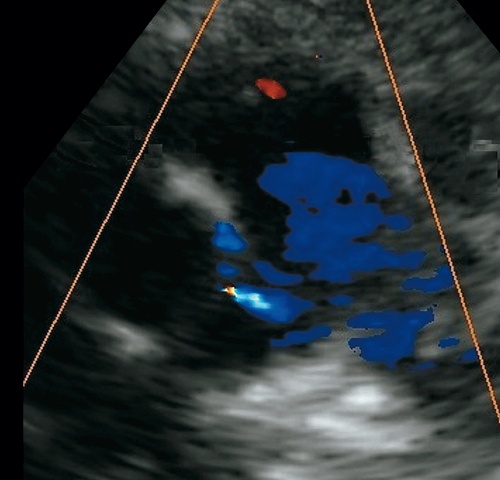

Наибольшие трудности в дифференциальной диагностике могут возникнуть в случае наличия патологических потоков в стволе ЛА (рис. 2–5), а также при дефекте межжелудочковой перегородки (ДМЖП, в этом случае должна проводиться дифференциальная диагностика с КФ в правом желудочке). При этом следует помнить об ЭхоКГ-характеристиках потоков при открытых артериальных протоках (ОАП) и легочной регургитации (см. рис. 2). «Злую шутку» при этом может сыграть исследование в CW-режиме. В таких ситуациях целесообразно пользоваться режимом цветового допплеровского картирования (ЦДК) и PW-допплеровского исследования, главным образом в тех случаях, когда имеет место наложение на ось сканирования нескольких цветовых, равнонаправленных и к тому схожих по фазе сердечного цикла потоков. Не стоит забывать об анатомических особенностях и наиболее частой локализации той или иной патологии.

a) парастернальная позиция короткая ось на уровне аортального клапана, ствола легочной артерии. Низкообъемный диастолический поток сброса крови направо на уровне проксимального отдела левой коронарной артерии в ствол легочной артерии. Поток к датчику.

б) парастернальная позиция короткая ось на уровне аортального клапана, ствола легочной артерии. Режим РW-допплеровского картирования. Регистрируется среднескоростной диастолический (!) поток сброса крови направо, Vmax 1,0 м/с, Gmax 4,0 мм рт.ст.

а) Парастернальная позиция короткая ось на уровне аортального клапана, ствола легочной артерии. Режимы В- и ЦДК. Низкообъемный патологический диастолический поток, направленный от датчика, в проекции ствола левой коронарной артерии и основания правой легочной артерии.

ЛА – легочная артерия, АК – аортальный клапан, КЛА – клапан легочной артерии.

б) Парастернальная позиция короткая ось на уровне аортального клапана, ствола легочной артерии. Увеличенное изображение.

в) Парастернальная позиция, короткая ось на уровне аортального клапана, ствола легочной артерии. В режиме CW- регистрируются среднескоростные равнонаправленные: систолический поток в стволе ЛА/проксимальном отделе правой легочной артерии (Vmax до 1,5 м/с, обозначен стрелкой «1») и диастолический поток из проекции коронарной фистулы, низкообъемный, с Vmax до 1,4 м/с (Gmax – 7,84 мм рт.ст., обозначен стрелкой «2»). Данные по Vmax и Gmax в проекции патологического потока практически идентичны показателям, приводимым S.-M.Hong и соавт. [19].